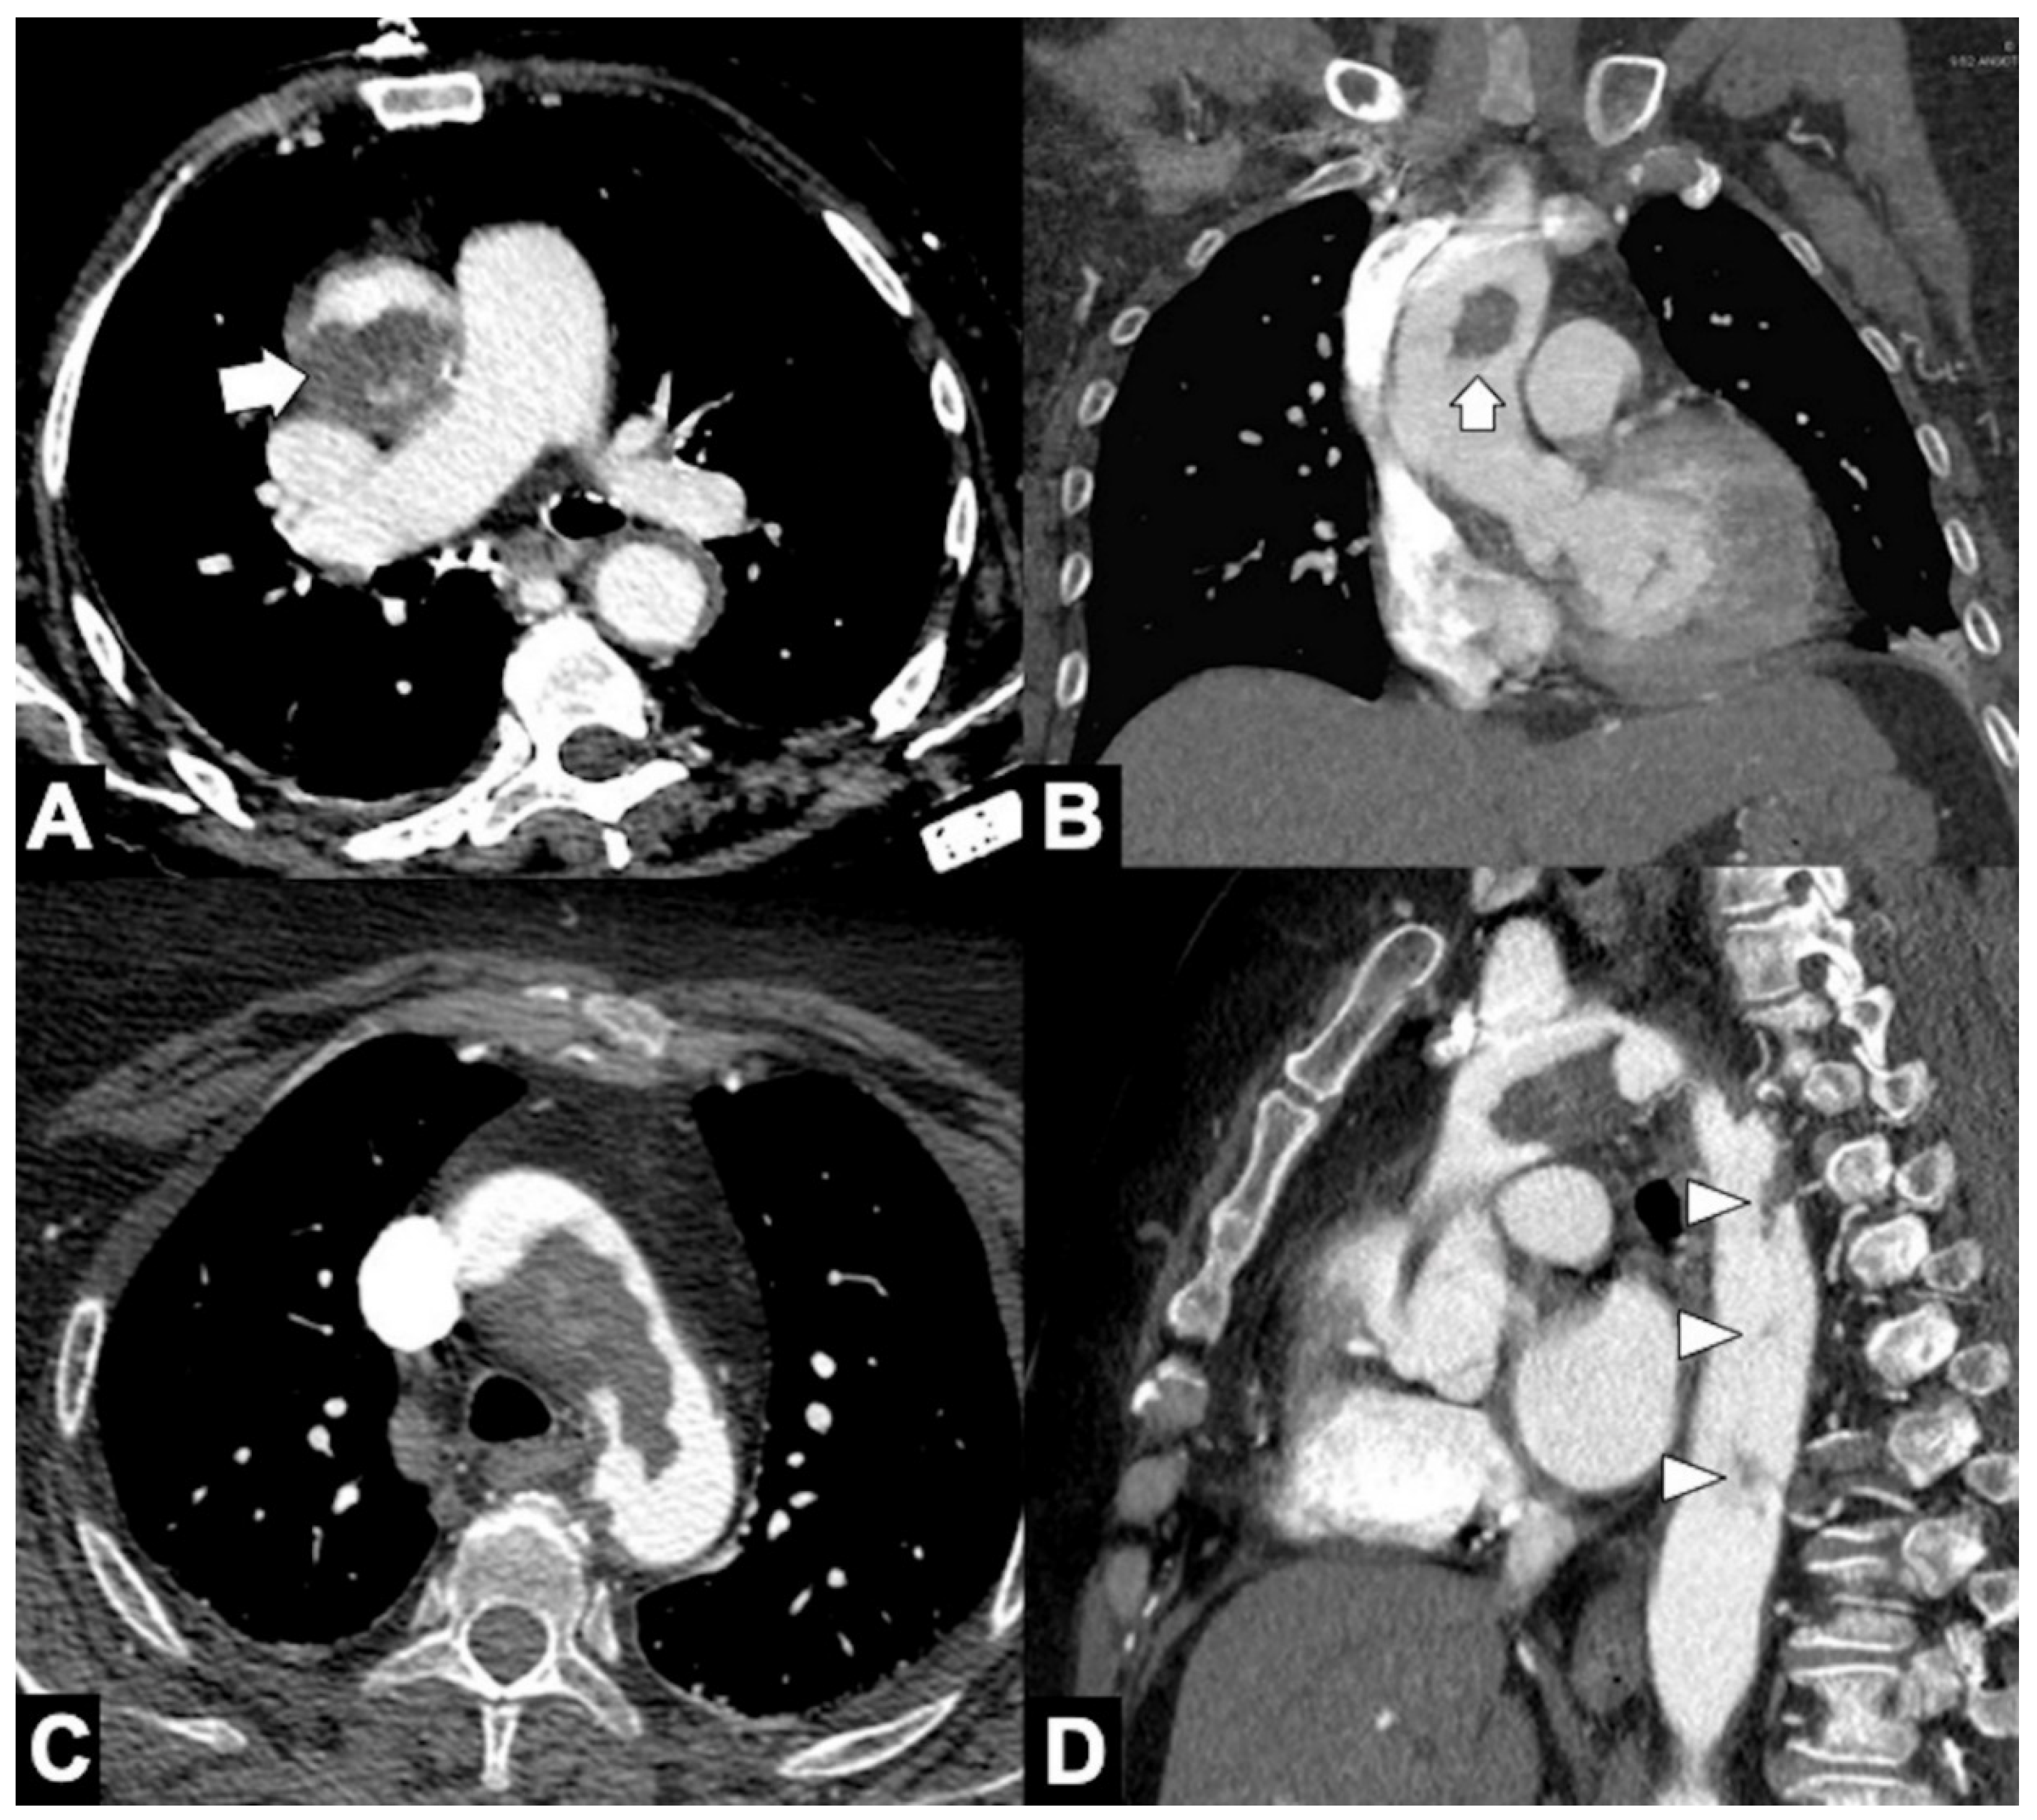

A low-dose, non-gated, non-contrast phase, with coverage from the lung apex to the lower abdomen, which is useful to evaluate the presence of aortic intramural hematoma, displaced intimal calcification, surgical material, and high-density pericardial, pleural, or mediastinal blood (Figure 2). The radiation dose of the non-contrast phase should be kept low by using wider collimation and low tube potential with concomitant reduction in the tube current. Nowadays, dual-source technology provides a virtual non-contrast phase obviating the need to acquire a non-enhanced phase.

Figure 2. Usefulness of CTA low-dose unenhanced phase in acute aortic syndrome. (A) Noncontrast CT axial scan shows dissection flap (arrow) and displaced intimal calcifications (arrowhead) in supra-aortic vessels extension of type A aortic dissection in a 79-year-old-man with acute neck and back pain. (B) Axial image from noncontrast CT shows a crescent-shaped high-density rind in the ascending aorta, a typical appearance of type A acute intramural hematoma (arrowheads). (C) Noncontrast CT axial scan shows a large bilateral pleural effusion with increased density in the dependent aspect of the collection (hematocrit sign), highly suggestive of hemothorax (asterisk) from rupture of the descending thoracic aorta aneurysm. (D) Axial image of aorta from noncontrast CT shows hemomediastinum tracking along the main and right pulmonary arteries and hyperattenuating dissection flap (arrowheads) in ascending aorta in a 68-year-old woman with ruptured type A dissection.